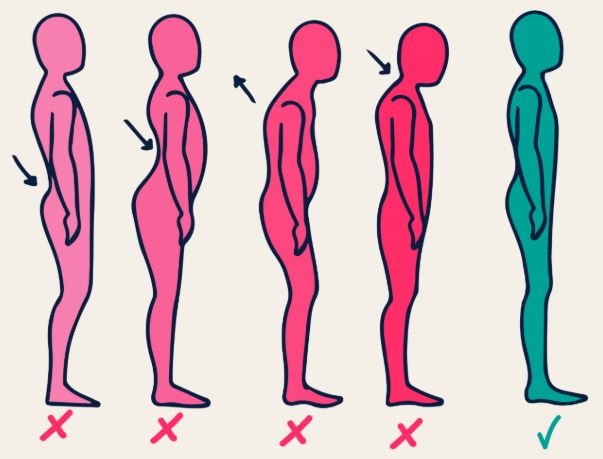

Devamını Oku »Duruş (postür) vücut kısımlarının diziliş ve düzenidir. Postür statik veya dinamik olarak ikiye ayrılır. Oturma, ayakta durma, yatma sırasında vücudun…

Devamını Oku »Servikal spondiloz yaşa, mesleki ve sportif zorlanmalara, duruş bozukluklarına bağlı olarak boyun omurgası eklemleri, diskleri, yumuşak dokuları ve kaslarının etkilendiği,…

Devamını Oku »Uzm. Dr. Ahmet Erzurumlu Bugün birçok kişi gün boyunca masa başında veya bilgisayar karşısında oturarak çalışmaktadır. Bunun doğal sonucu olarak kilo…